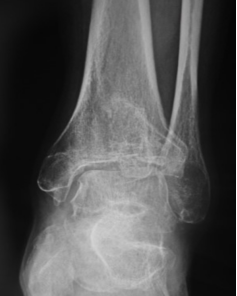

目前应用最广的是踝关节骨关节炎分期为Takakura-Tanaka分期:

0期:踝关节平行,无关节炎征象;

Ⅰ期:踝关节平行,无关节间隙狭窄,有早期软骨下骨硬化或骨赘形成;

Ⅱ期踝内侧关节间隙狭窄,无软骨下骨接触;

Ⅲ期又可分Ⅲa期和Ⅲb期:

Ⅲa期 踝内侧间隙消失,软骨下骨接触面局限于内侧;

Ⅲb期 踝软骨下骨接触延伸至距骨穹窿部;

Ⅳ期 踝关节间隙消失伴全部软骨下骨接触。

影像学检查:最重要的诊断依据:如X片检查、CT检查、MRI检查、超声波检查等,其中X片及CT对诊断尤为重要。

X片:检查可以显示关节间隙狭窄、骨赘形成、软骨下骨硬化等特征性表现;